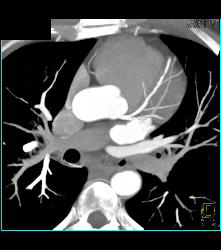

Normal Left Anterior Descending Coronary Artery (LAD)